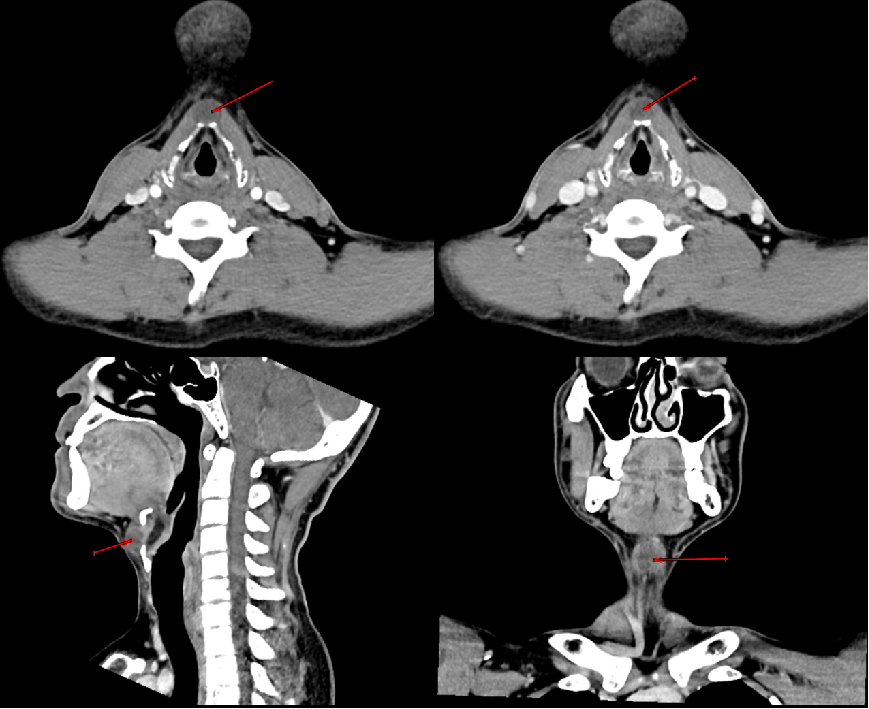

2.CT检查

◆ 平扫表现:显示为颈前正中线附近圆形或类圆形低密度影,边界清楚,密度均匀,近似水样密度。周围组织可受压移位。

◆ 增强扫描表现:囊壁可有轻度强化,囊内容物无强化。伴感染时,囊壁可增厚并明显强化。